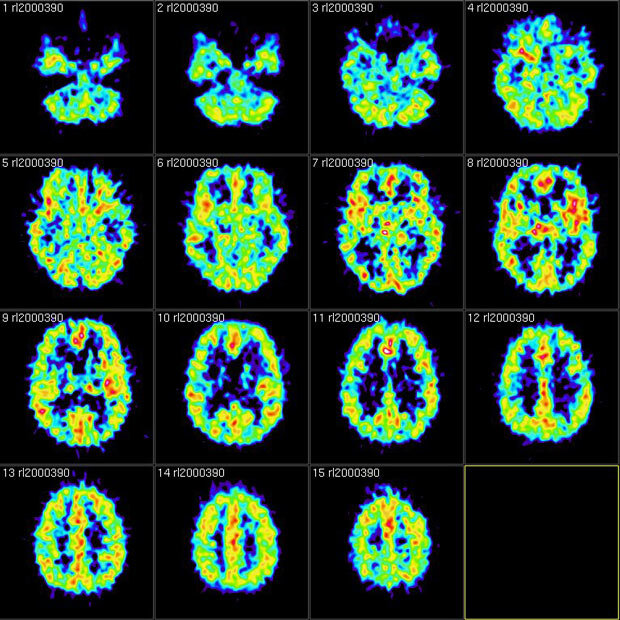

Результаты сканирования методом позитронно-эмиссионной томографии

Reigh LeBlanc / Flickr

Результаты сканирования методом позитронно-эмиссионной томографии Reigh LeBlanc / Flickr